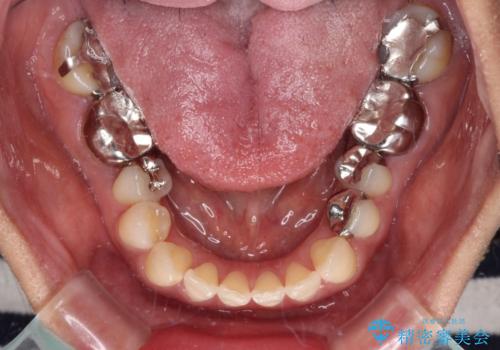

- 矯正治療を行ったものの、隙間やデコボコが多く、欠損している前歯も気になるとのことで来院された患者様です。

当初はセラミック治療だけを希望されていましたが、上下前歯のデコボコが顕著であったため、セラミッククラウンにて治療する前に再度矯正治療を行った方が仕上がりがきれいになると説明し、再矯正を行うこととしました。

舌突出癖により、上下前歯が突出して離開してしまったため、舌のトレーニングを徹底的に行いました。